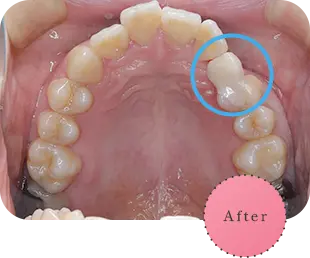

Before

After

主訴

上の前歯が抜けそう

治療期間

6か月

治療費

30万円

治療内容

右上1番を抜歯後に骨と歯茎を増やし、隣の歯の裏側を少量削り、接着性ブリッジにて修復

治療のリスク

咬み合わせによっては、セラミックが欠ける可能性があります。